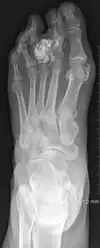

| Non-cancerous | Subungal exostosis[2] | ![]() |